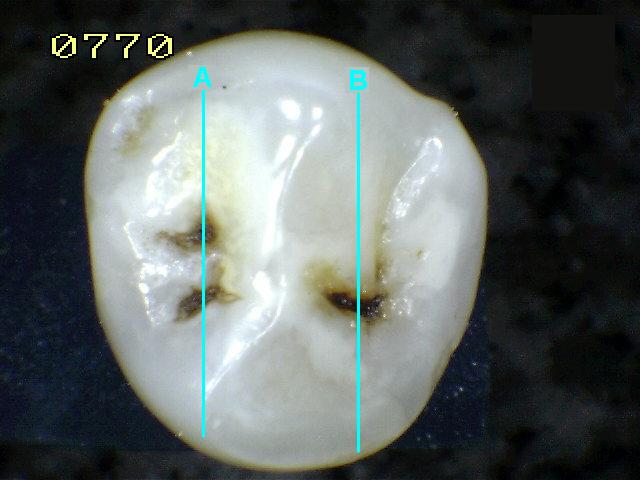

Espécimen Nº

36 |

| Corte sagital A:

Código 0

Corte sagital B : Compatible con

código 1

histológico |